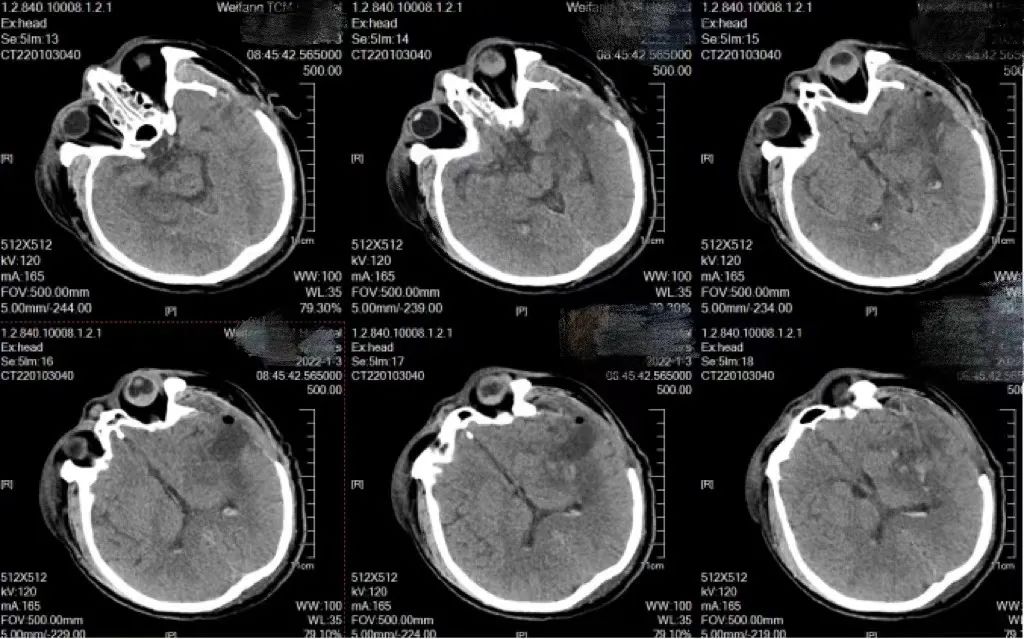

2021年12月,患者姜先生突发右侧肢体活动不利伴言语不能入院治疗。颅脑CT示左侧外囊出血,量较少,保守治疗。次日清晨患者出现肢体活动变差,昏迷,复查颅脑CT出血较前增加,大块血肿压迫脑组织,病情危重。

术后复查颅脑CT血肿清除满意,由于患者患有严重的肾衰,血钾报危急值,大大增加了患者的治疗难度,术后当天科室与血液透析室共同分析沟通病情,制定个体化透析方案,提供床旁血液净化。